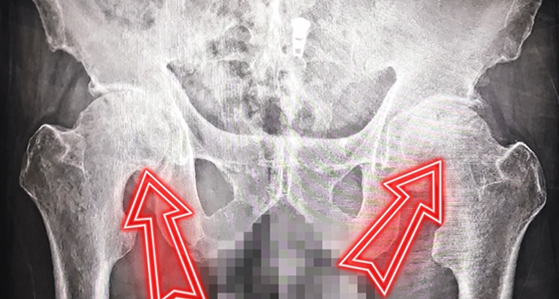

家住山东莱芜的李大爷,曾被双侧股骨头坏死折磨多年。疼痛与跛行如影随形,别说远走,就连日常走路都举步维艰,出门走不了两里地,甚至连弯腰穿鞋、穿袜这样的小事都难以独立完成,生活质量大打折扣。2025年10月,抱着“能正常走路”的期盼,李大爷慕名来到济南关节外科医院寻求治疗。

入院后,医院专家团队为李大爷进行了全面细致的检查评估,明确其符合髋关节置换手术指征。针对患者病情与身体状况,团队经过周密术前研讨,最终决定采用骨科机器人辅助髋关节置换术,以毫米级精准度为患者重建健康关节。2025年10月、11月,李大爷先后顺利完成左侧、右侧髋关节置换手术,两场手术均圆满成功。